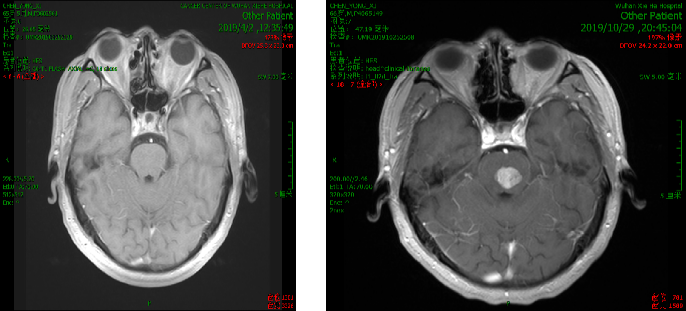

2019.10.18 当地医院头部MRI示:脑干区异常信号,约11mm*15mm,考虑转移瘤合并脑卒中。

脑部蛋氨酸PET示:脑桥结节,蛋氨酸代谢异常增高,SUVmax 4.51,考虑转移性恶性肿瘤。

影像科、神经内科会诊,考虑脑部病灶为肠癌转移病灶。

脑干转移病变,合并瘤卒中,周边水肿。

处理:2019.11.5至2019.11.10行射波刀放疗,DT 20GY/4F,同步替莫唑胺化疗。

10天后复查脑部CT提示病灶变化不明显,出血量无增加,水肿无增加。

处理:再次射波刀追加剂量,DT 20GY/4F,贝伐珠单抗200mg治疗一次。

效果:患者脸部麻木及右侧肢体麻木症状改善明显,肌力IV级,可独自行走。